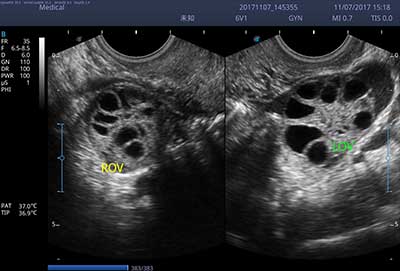

一键自动优化